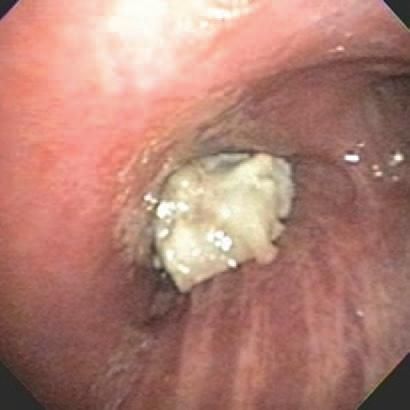

Flexible bronchoscopy showed an irregular, polypoidal, whitish mass occluding the bronchus intermedius (Figure 2). The pathology results were nonconclusive, and culture results were negative. Rigid bronchoscopy and a biopsy specimen of the mass showed spindle cells with scant dense stroma, suggesting synovial sarcoma.

Figure 2 –

Flexible bronchoscopy shows an irregular, polypoidal, whitish mass occluding the bronchus intermedius.